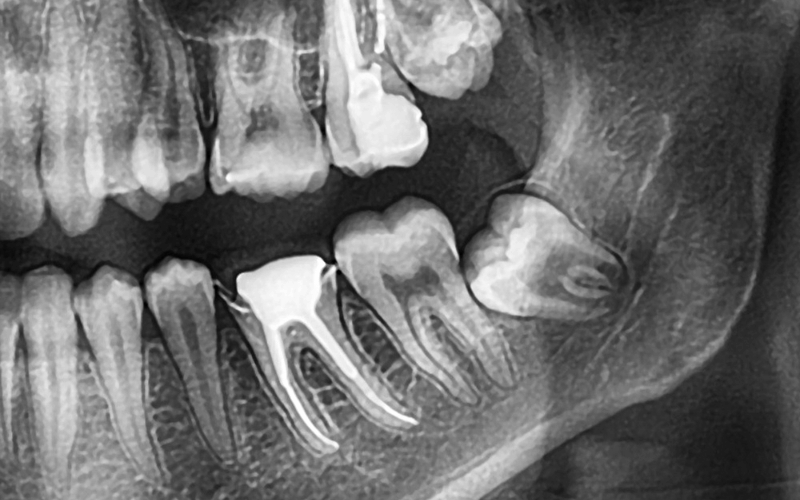

1. Impaction: It occurs when there’s not enough space in the jaw for the wisdom tooth to erupt correctly. Impacted teeth can grow at an angle, pushing against other teeth or becoming stuck under the gum tissue. Pain, swelling, and infections are the major symptoms.

3. Damage to other teeth: Impacted wisdom teeth can crowd or damage surrounding teeth, leading to misalignment, bite problems, and tooth loss.